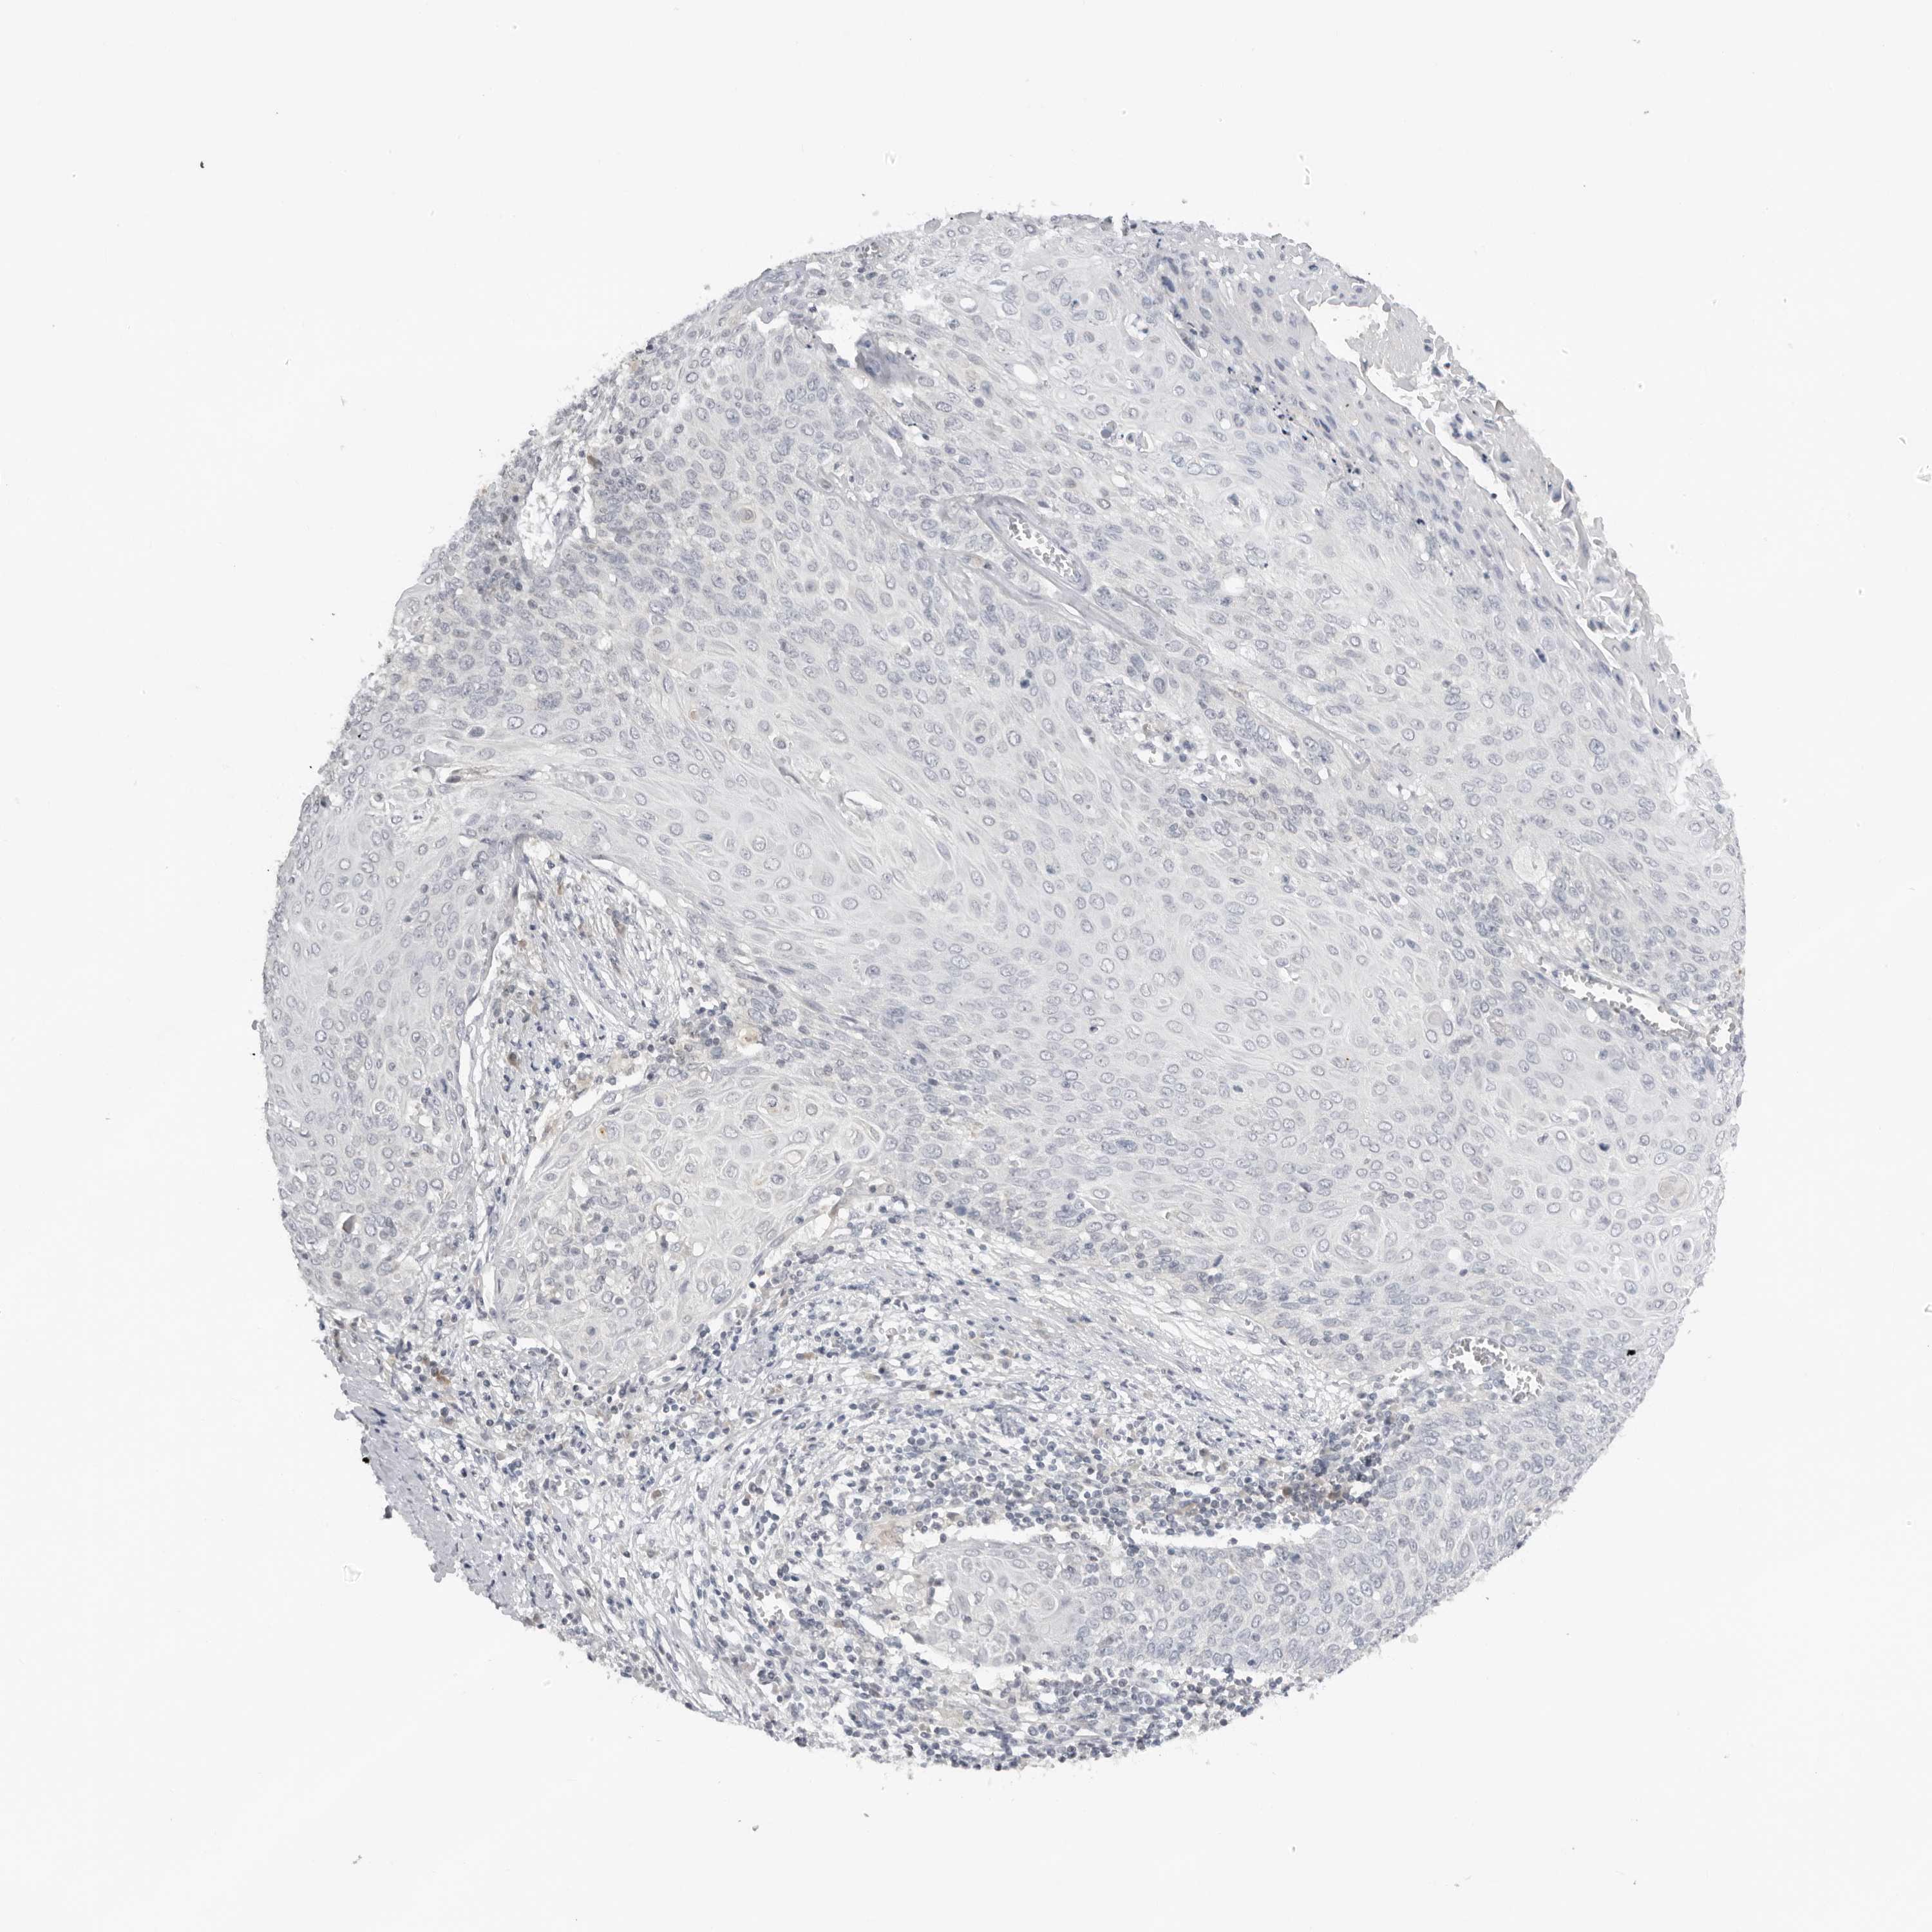

CERVICAL CANCER - Protein expressioni

A mouse-over function shows sample information and annotation data. Click on an image to view it in a full screen mode. Samples can be filtered based on level of antibody staining by selecting one or several of the following categories: high, medium, low and not detected. The assay and annotation is described here.

Note that samples used for immunohistochemistry by the Human Protein Atlas do not correspond to samples in the TCGA dataset.

Antibody stainingi

Antibody staining in the annotated cell types in the current human tissue is reported as not detected, low, medium, or high, based on conventional immunohistochemistry profiling in selected tissues. This score is based on the combination of the staining intensity and fraction of stained cells.

Each image is clickable and will lead to virtual microscopy that enables deeper exploration of all samples and also displays staining intensity scores, fraction scores and subcellular localization as well as patient and tissue information for each sample.

Antibody HPA028560

Staining

High

Medium

Low

Not detected

Intensity

Strong

Moderate

Weak

Negative

Quantity

>75%

75%-25%

<25%

None

Location

Nuclear

Cytoplasmic/membranous

Cytoplasmic/membranous,nuclear

Squamous cell carcinoma, NOS

Adenocarcinoma, NOS